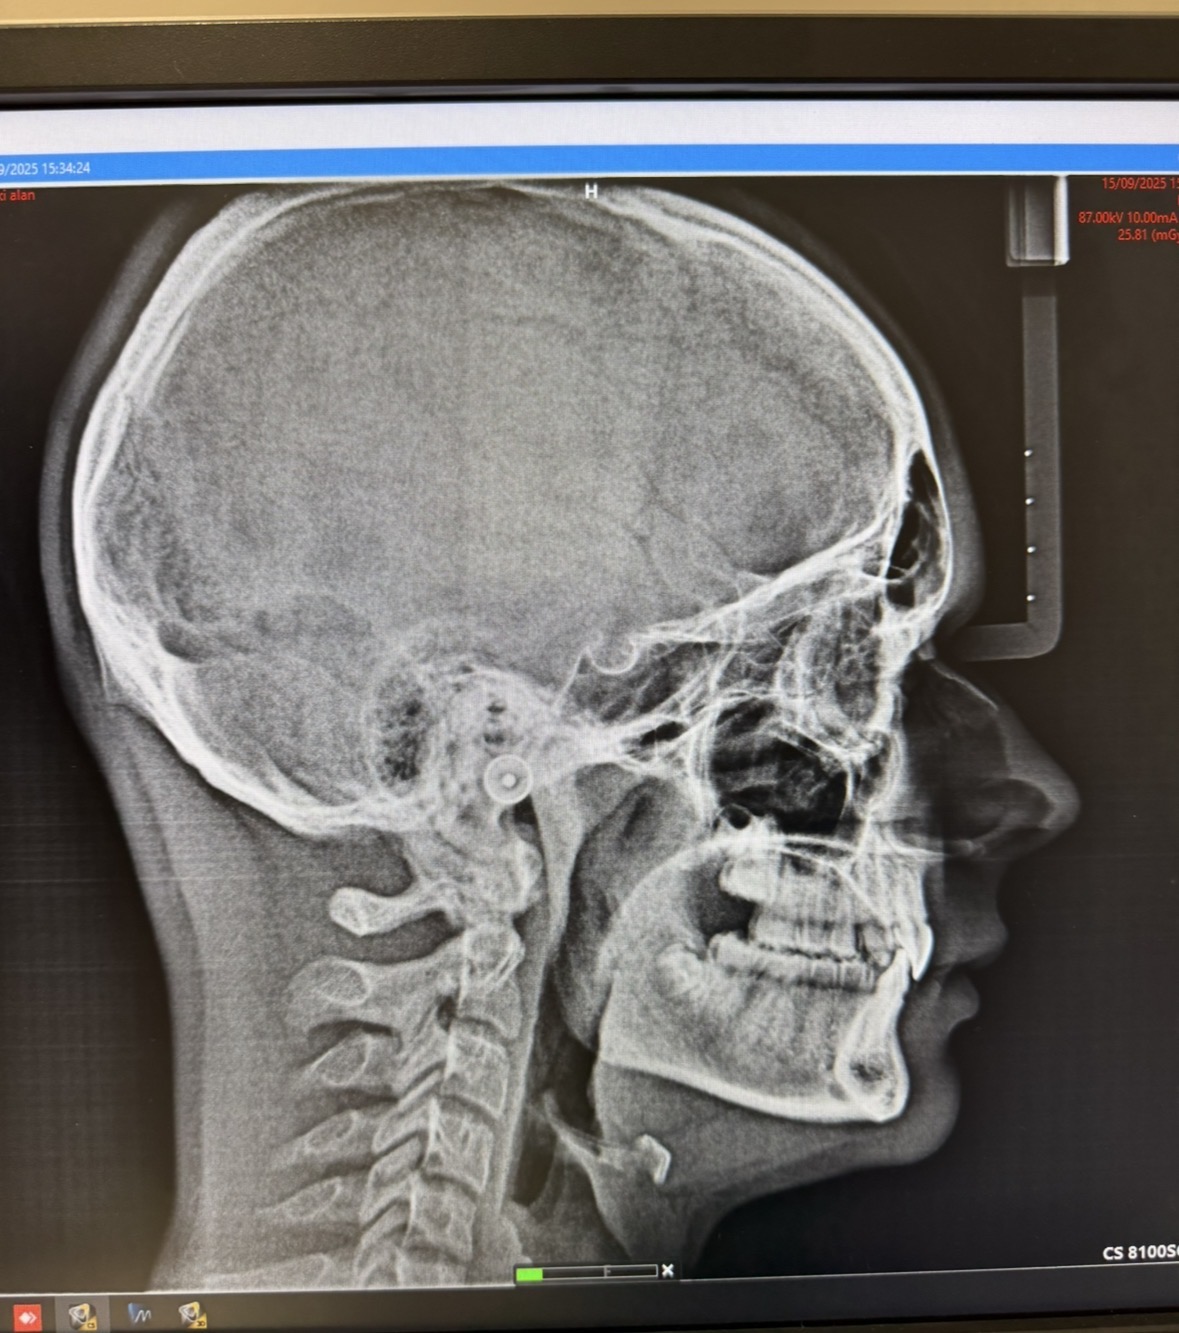

idk if I’m recessed and what needs fixing and shit. Also yeah I know I have an overbite cuz of the teeth but ima get that fixed soon

The ortho I have said braces since my SNA is 82° and SNB 80° he said the overbite is caused just by teeth, but I don’t know if it’ll make my bones worse. I need a bone anchored expander anyway so I could try ask for that face pull mask thing. I don’t know if there’s any other